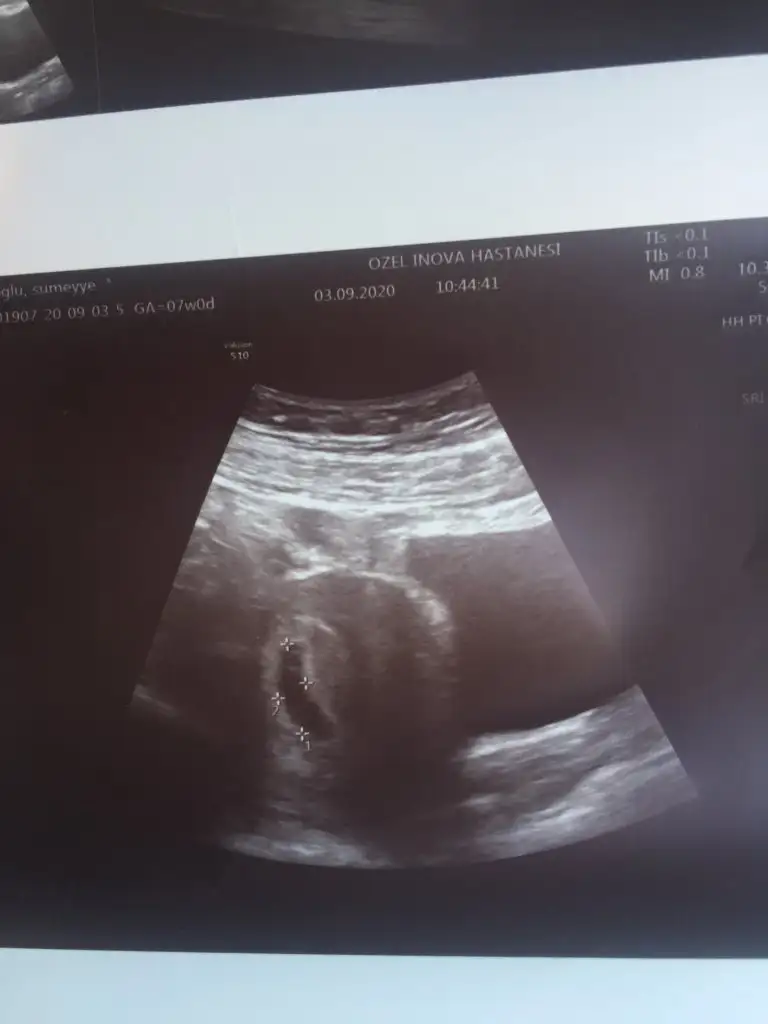

Canım hoşgeldinSevgili anne adayları herkese merhaba ben iki gün önce test yaptım ve anında pozitif çıktı bu gün de doktora gittim doktor keseyi gördü 7 haftalık dedi haftaya kalp atışını duycakmışız ama ben şimdi yeni evliyim hiç bişey bilmiyorum acaba tecrübeli anneler bana yardımcı olabilirler mi neler yapmam gerekiyor benim çok çok heyecanlıyım

Folik asite bu gün başladım ama benim aşırı koku hassasiyetim var midem gün boyunca bulanıyo daha hiç bişey yaptırmadım ne yaptırmam gerekiyor acaba bi de kesem buCanım hoşgeldin ☺ Hayırlı uğurlu olsun Allah sağlıkla kucağına almayı nasip etsin inşallah ❤

hayirli olsun bebegin:) kalp atisini duyduktan sonra doktorun rutinleri ister, o zaman yaptirirsin. simdilik folik asit icmekten, dengeli beslenmekten, yorucu isler yapmamaktan baska yapman gereken pek bir sey yokFolik asite bu gün başladım ama benim aşırı koku hassasiyetim var midem gün boyunca bulanıyo daha hiç bişey yaptırmadım ne yaptırmam gerekiyor acaba bi de kesem bu Eki Görüntüle 2684562